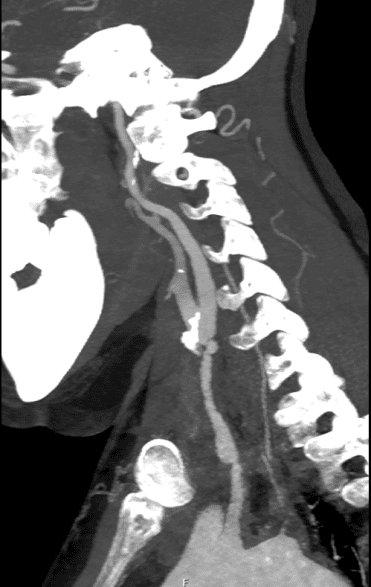

Resim. 30 yaşında takayasu bulunan kadın hastanın beyin ve kola giden damarlardaki tutulumu

Hastalığa bağlı olarak çıkan aortada daha fazla olmak üzere dilatasyon veya anevrizma gelişebilmektedir.